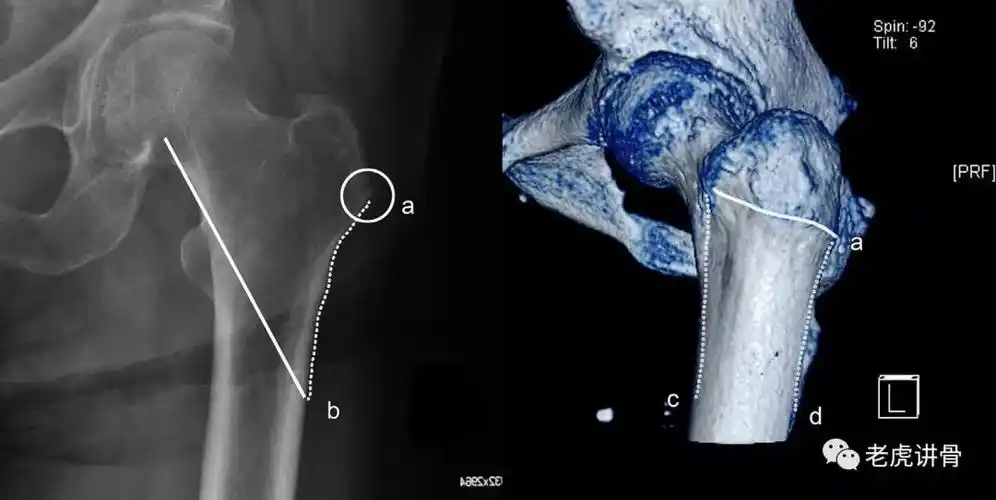

股骨近端骨折:合并外侧壁骨折,内固定要小心